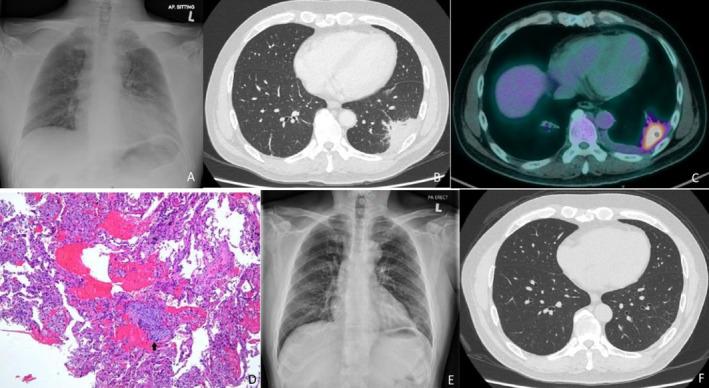

Organising pneumonia (OP) is a distinct pathological pattern characterised by the presence of granulation tissue buds composed of fibroblasts and myofibroblasts embedded in a loose connective tissue matrix within the distal pulmonary airspaces. When OP occurs without an identifiable cause or etiologic context, it is termed cryptogenic organising pneumonia (COP). The diagnosis of OP can be challenging due to its diverse clinical presentations, including the idiopathic form and various secondary forms associated with underlying diseases. We report a case of a middle-aged male presenting with intermittent cough and haemoptysis. Initial sputum analysis was unremarkable, and the patient showed no improvement with antibiotic therapy. Chest radiography showed left lower zone consolidation. Computed tomography (CT) thorax revealed a mass in the left lower lobe, while positron emission tomography-computed tomography (PET/CT) demonstrated a hypermetabolic lesion at the same site. Bronchoscopic bronchoalveolar lavage was negative for tuberculosis, respiratory pathogens, and malignancy. Autoimmune screening yielded negative results. A transthoracic tru-cut lung biopsy confirmed the diagnosis of OP. The patient was treated with prednisolone, leading to significant clinical improvement and complete resolution of the lesion on follow-up CT imaging.

机化性肺炎(OP)是一种独特的病理模式,其特征是在远端肺气腔内由成纤维细胞和肌成纤维细胞组成的肉芽组织芽嵌入疏松结缔组织基质中。当OP发生时无明确病因或病因背景时,称为隐源性机化性肺炎(COP)。由于OP临床表现多样,包括特发性形式和与基础疾病相关的各种继发性形式,其诊断可能具有挑战性。我们报告一例中年男性,表现为间歇性咳嗽和咯血。初始痰液分析无异常,患者接受抗生素治疗后无改善。胸部X线显示左下肺实变。胸部计算机断层扫描(CT)显示左肺下叶有一肿块,而正电子发射断层扫描-计算机断层扫描(PET/CT)显示同一部位有高代谢病变。支气管镜下支气管肺泡灌洗未发现结核、呼吸道病原体及恶性肿瘤。自身免疫筛查结果为阴性。经胸壁穿刺肺活检确诊为OP。患者接受泼尼松龙治疗,临床症状显著改善,随访CT影像显示病变完全消退。